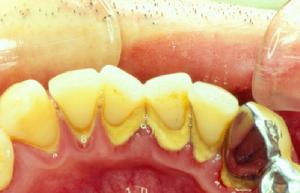

以齦緣為界,根據牙石沉積的部位,分為齦上牙石和齦下牙石。

齦上牙石,又稱唾石,是位於齦緣以上臨床牙冠表面上的牙石,肉眼可以直接看見。其礦化物質來源於唾液,因此在唾液腺導管開口處相應處的牙面上常常沉積較多,即在腮腺導管開口處相應的上頜第一磨牙頰面,頜下腺和舌下腺導管開口處相應的下頜前牙舌面容易沉積牙石。齦上牙石多呈黃色或白色,也可以由於吸菸或食物著色而呈深色。

齦下牙石又稱為血石,沉積於齦緣之下,附著在齦溝或牙周袋內的根面,肉眼不可以直接看見,大塊齦下牙石可以在X線片上顯示。其礦化物質來源於齦溝液,一般呈褐色或黑色,與牙面的附著較齦上牙石更牢固。